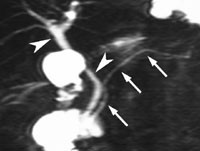

Hos sju pasienter var indikasjonen sphincter Oddi-dysfunksjon, slik dette er definert av Toouli og medarbeidere (4). Hos to av disse oppstod det under sekretinstimulering sterke buksmerter av samme type som de tidligere hadde hatt. Samtidig ble galle- og pancreasgangen patologisk dilatert (fig 1a, 1b), mens den duodenale sekretfyllingen var forsinket. Pasientene ble henvist til papillotomi, og de har deretter vært symptomfrie i henholdsvis åtte og 16 måneder. Det viste seg ved S-MRCP at to av pasientene hadde pancreas divisum. ERCP var gjort på forhånd hos begge, men bare gallegangen var fylt, og anomalien var derfor ikke erkjent. To pasienter viste normale funn og ingen smerte, konklusjonen ble således ingen dysfunksjon. Den siste pasienten i denne gruppen hadde spist umiddelbart før S-MRCP (på tross av informasjon om å faste). Dette er altså en mislykket S-MRCP, som ikke bidrog med ny informasjon.

Sphincter Oddi-dysfunksjon er en vanskelig tilstand å diagnostisere. Ofte har pasienten vedvarende smerteanfall etter kolecystektomi. Tilstanden kan klinisk til forveksling likne et choledochuskonkrement med spontan avgang. Smerteanfallene kommer imidlertid tilbake, til tross for at stein i dype galleveier ikke påvises. Årsaken er at patologisk motilitet i sphinctermuskulaturen er den etiologiske bakgrunn for plagene. Det er publisert flere detaljerte kriterier for denne tilstanden (4 – 6). En av de refererte pasienten med denne indikasjonen (fig 1a, 1b) illustrerer at S-MRCP kan bidra til en betydelig bedring i den diagnostiske sikkerhet. Ytterligere sikkerhet kan oppnås etter sphincterotomi, hvis sekretinstimulering da ikke gir smerteanfall og dilatasjon av gangsystemet.